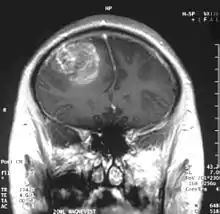

Glioblastoma - MR coronal with contrast

Somasundaram's work is centered around the studies of oncoviruses, tumor suppressor genes, gliomas and microRNAs and he has done advanced research on glioblastoma, an aggressive form of cancer affecting the brain.[8][9] The group led by him is engaged in work concerning the determination of the role of cellular tumor antigen p53 in glioma, regulating the protein, p73 in cervical cancer patients, using Adenovirus early region 1A, a tumor suppressor gene, the analytical study of BRCA1 gene in breast cancer and the analysis and regulation of SV2A, a synaptic vesicle protein.[3] He demonstrated that glioblastoma spreads rapidly by producing macrophage colony-stimulating factor (MCSF) in large quantities which in turn stimulate the growth of blood vessels in the tumor.[10] He proposed that the MCSF interacted with the anti-tumor microglial cells of the human body and induced them to produce Insulin-like growth factor-binding protein 1 (IGFBP1), thereby impairing the capacity of microglial cells to fight the tumor cells, a process he called befriending. The discovery of this new molecule, IGFBP1 and its role in glioma angiogenesis, led to a collaborative investigation which involved four research institutions namely National Institute of Mental Health and Neuro Sciences, Sri Sathya Sai Institute of Higher Medical Sciences and Institute for Functional Genomics (INSERM) of the University of Montpellier, apart from the IISc.[11] The research team led by Somasundaram and Phillipe Marin of INSERM validated the earlier findings and proposed a new therapeutic protocol for glioblastoma which targeted IGFBP1, rather than Vascular endothelial growth factor (VEGF) which earlier treatment methods attacked.[12] The researchers, later, released their findings through a paper, Glioblastoma-derived Macrophage Colony Stimulating Factor (MCSF) Induces Microglial Release of Insulin-like Growth Factor-Binding Protein 1 (IGFBP1) to Promote Angiogenesis, published in the Journal of Biological Chemistry.[13] Work is in progress at his laboratory for developing biomarkers (twenty genes of which is named gene X, have already been discovered)[14] for which detailed study is being conducted on microRNA, DNA methylation, modifications of chromatin and gene fusions.[4][15] His studies have been documented by way of a number of articles[16][17][note 1] and ResearchGate, an online repository of scientific articles has listed 178 of them.[18] He has also conducted workshops[19][20][21] including the Workshop on Next Generation Sequencing organized by the Council of Scientific and Industrial Research in November 2013[22] and has delivered invited or plenary speeches at various conferences and seminars[23] and the 5th annual meeting of the Proteomics Society, India held in September 2013 was one among them.[24]